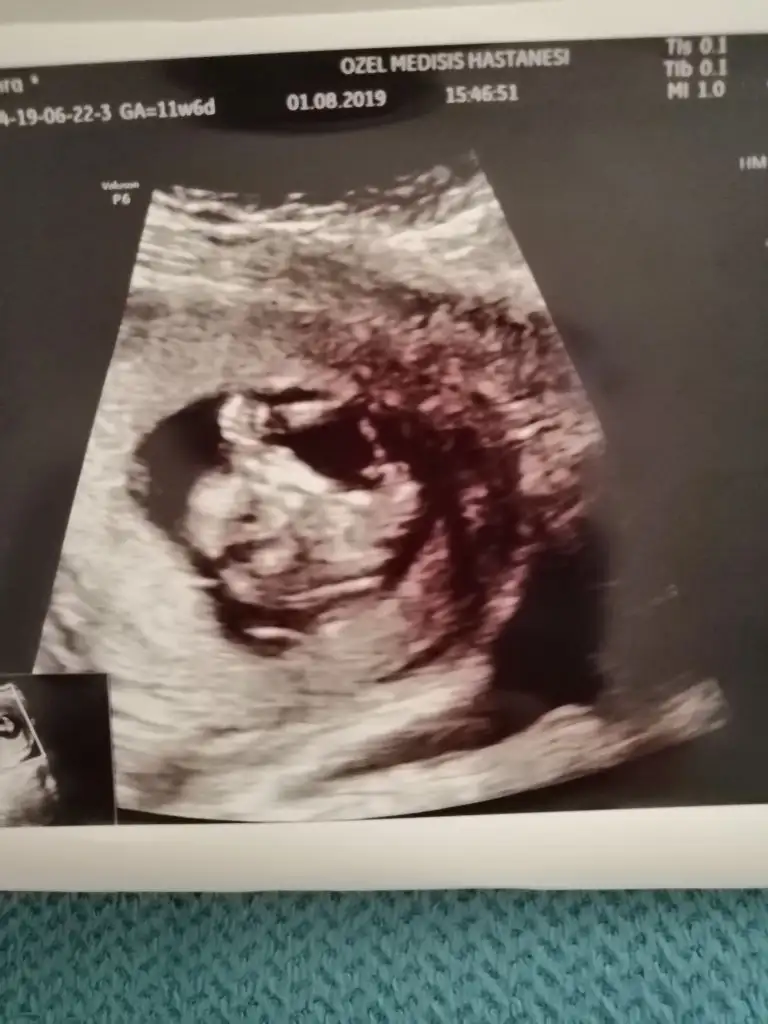

Tamam kız bu bebiş.kesin kızEki Görüntüle 2294615 Eki Görüntüle 2294617

Bunlarda az önce alınan resimler normalde 11 hafta 6 günlük ama usg de 12 hafta 6 günlük

Doktor %80 erkek dediTamam kız bu bebiş.kesin kız![]()

Bence kız.bir sonraki kontrolde daha da kesinleşecektir.ben ısrarla kız diyorumDoktor %80 erkek dedi

Siz erkek istiyordunuz galiba.nub çizgisine ve kafa yapısına göre yorum yapıyorum.cinsiyet oluşmadan önce nub çizgisi oluşur.bu çizgi paralelse kız,dik ise erkek demektir.sizin bebeğinizin nub çizgisi bariz paralel.kafa yapısı da oval.erkeklerin kafa yapısı daha yuvarlak olur. Doktor kesin erkek dedi mi size? Buda cinsel organı diye gösterdi mi? Kaç haftalıksınız şuan?Doktor organını bile gösterdi bu çıkıntı olabilir diye yine de cevabınız için teşekkür ederim merakımdan soruyorum yanlış anlamayın neye göre Tahminde bulunuyorsunuz mesela son resim tam olarak neyi gösteriyor hiçbirşey anlamadım

Evet gönlümden geçen erkek Bi tane kızım var çok ta sevinmiştim siz şimdi kesin kız deyince moralim bozuldu biraz. Şu an sat a göre 11 hafta 6 gün usg ye göre 12 hafta 6 gün. Doktor erkeğe çok benziyor çıkıntısı burada diyerek gösterdi kesin erkek demedi yüzde 80 erkek dedi ama bazen kızlarda da bu çıkıntı oluyor dedi. Hatta bu Nub teorisinden de bahsettim belli olmaz bazen dik bazen paralel bile olabilir dediSiz erkek istiyordunuz galiba.nub çizgisine ve kafa yapısına göre yorum yapıyorum.cinsiyet oluşmadan önce nub çizgisi oluşur.bu çizgi paralelse kız,dik ise erkek demektir.sizin bebeğinizin nub çizgisi bariz paralel.kafa yapısı da oval.erkeklerin kafa yapısı daha yuvarlak olur. Doktor kesin erkek dedi mi size? Buda cinsel organı diye gösterdi mi? Kaç haftalıksınız şuan?

Erkek gibi.duruş pozisyonu dik olunca kız mı erkek mi karar veremedim açıkçası.ama oyumu erkekten yana kullanıyorum. Kız da olabilir ama.ay emin olamadım bu usg deyok yok kız bu

Kızlarda da bu çıkıntı oluyor dediyse nub çizgisinden bahsediyor.11 12 haftada cinsel organ tam anlamıyla oluşmuyor nub çizgisi oluyor.13 14 haftalarda organ oluşmuş oluyor.yani direkt olarak pipi göstermemiş.bilmiyorum doktor erkek dediyse erkek olabilir.ben bariz kız görüyorum bu usg de.elbette doktorlar daha iyi bilir tabi.rabbim gönlünüzdekileri nasip etsin inşallah.siz sorduğunuz için cevapladım.ama bana göre bu bebiş kızEvet gönlümden geçen erkek Bi tane kızım var çok ta sevinmiştim siz şimdi kesin kız deyince moralim bozuldu biraz. Şu an sat a göre 11 hafta 6 gün usg ye göre 12 hafta 6 gün. Doktor erkeğe çok benziyor çıkıntısı burada diyerek gösterdi kesin erkek demedi yüzde 80 erkek dedi ama bazen kızlarda da bu çıkıntı oluyor dedi. Hatta bu Nub teorisinden de bahsettim belli olmaz bazen dik bazen paralel bile olabilir dedi